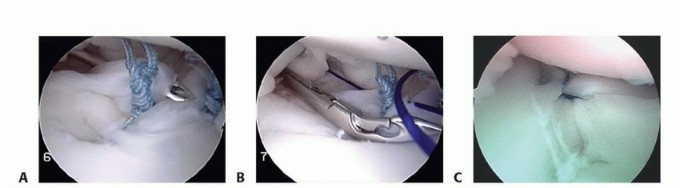

Anchor Placement and Suture Passing

Anchor placement begins at the most inferior aspect of the tear, typically at the 5:30 position for a right shoulder. This foundational anchor is the most critical; it dictates the tension of the inferior glenohumeral ligament and the success of the entire shift. The drill guide is introduced through the anteroinferior portal, ensuring a trajectory that bisects the glenoid face to avoid joint penetration (the "deadman's angle"). We utilize modern biocomposite or all-suture anchors, typically 2.4mm to 3.0mm in diameter, to minimize bone removal while maximizing pull-out strength.

Image

Once the anchor is deployed, suture passing is executed to achieve a distinct inferior-to-superior and medial-to-lateral shift of the capsulolabral tissue. Various passing devices can be utilized, including curved suture lassos or direct penetrating devices. The device is passed through the capsule first, inferior and medial to the anchor, and then through the labrum.

This "pinch" of tissue ensures that when the knot is tied (or the knotless mechanism is tensioned), the capsule is plicated and drawn up onto the articular margin, recreating the essential bumper effect. Subsequent anchors are placed sequentially moving superiorly along the anterior rim, typically at the 4 o'clock and 3 o'clock positions, depending on the extent of the lesion.

Knot Tying, Capsular Plication, and Construct Finalization

If utilizing knotted anchors, arthroscopic knot tying must be precise to avoid creating prominent knot stacks that can abrade the articular cartilage of the humeral head. We typically utilize a sliding, locking knot (such as a Weston or SMC knot) followed by three alternating half-hitches on alternating posts. The post limb must be the one that exits the anchor directly, ensuring the knot sits securely on the labral tissue, compressing it against the decorticated bone bed.

As each knot is tied, the surgeon must visually confirm the restoration of capsular tension and the recreation of the labral bumper. The axillary pouch should appear visibly reduced in volume, and the humeral head should be centralized within the glenoid fossa.